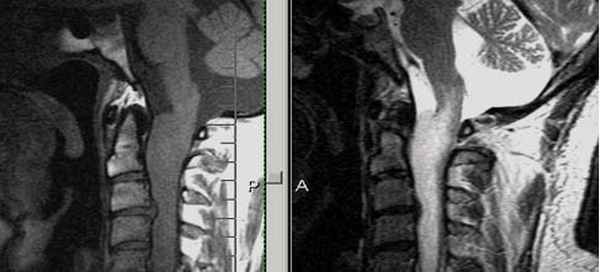

Атланто-дентальное сочленение достаточно часто подвергается повреждению у пациентов с ревматоидным артритом. Воспалительные изменения в суставе способствуют развитию эрозивных изменений зубовидного отростка, декальцификации и ослаблению связочного аппарата. Это может провоцировать развитие подвывиха или вывиха сустава, в том числе с компрессией мозговых структур.

При МРТ - исследовании четко визуализируется положение зубовидного отростка, состояние мягкотканых структур, степень паннуса, последствия подвывиха или вывиха (состояние спинного и продолговатого мозга, окружающих мягких тканей).